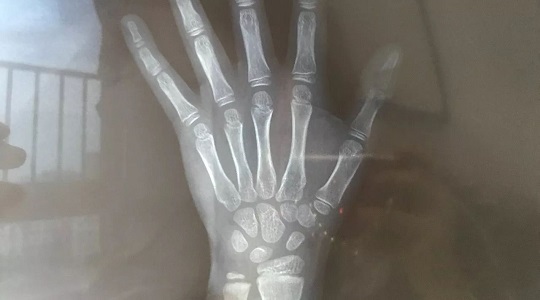

我家小伙子最終被預(yù)測(cè)出將來個(gè)子可能在174CM左右。這個(gè)數(shù)據(jù)是醫(yī)生根據(jù)“年齡身高”、“骨齡身高”、“遺傳身高”以及“體重”等多方因素綜合得出的。

從下圖右邊的橫向柱狀圖可以看出,我兒子的“年齡身高”最加分,也就是9歲男孩139這個(gè)身高在全國(guó)孩子中處于70%以上水準(zhǔn)。骨齡拍出的片子顯示正常,因此得分54%,屬于中等。最最減分的是他的“遺傳身高”,因?yàn)閶寢屚乳L(zhǎng)不爭(zhēng)氣,所以在這項(xiàng)上他只得分30%。